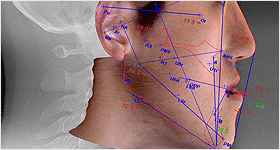

KAVO 3D CT Àåºñ¸¦ ÀÌ¿ëÇØ ÀÔüÀûÀ̰í Á¤È®ÇÑ µ¥ÀÌÅ͸¦ ¼öÁý¡¤ºÐ¼® ÇÑ ÈÄ, ÃëÇÕµÈ ÀڷḦ Åä´ë·Î ´ç½Å¸¸À» À§ÇÑ ÃÖÀûÀÇ E-lineÀ» ã¾Æµå¸³´Ï´Ù.

Morpheus 3D ½ºÄ³³Ê¸¦ ÀÌ¿ëÇÑ ÀÓ»ó °Ë»ç ¹× µÎºÎ±Ô°Ý¹æ»ç¼± »çÁøÀÇ ºÐ¼®À» Åä´ë·Î ¼ö¼ú °èȹÀ» ¼¼¿ì°Ô µÇ¸ç, °¡»ó¼ö¼úÀ» ½ÃÇàÇÏ¿© ¼ö¼ú ½Ã »ý±æ ¼ö ÀÖ´Â ¹®Á¦Á¡À» ¹Ì¸® ÆÄ¾ÇÇϰíÃÖÁ¾ ±³ÇÕ »óŸ¦ ±â·ÏÇÑ ½ºÇÁ¸°Æ®¸¦ Á¦ÀÛÇÏ¿© ¼ö¼ú ÈÄÀÇ ÃÖÁ¾ ¾È¸ð µîÀ» ¿¹ÃøÇÒ ¼ö ÀÖ½À´Ï´Ù.